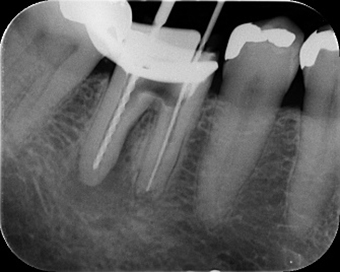

次に、レントゲン写真です。

左から2番目の歯が腫れている歯になります。

黄色の範囲で根の先が黒っぽくなっていて、細菌が炎症を引き起こしている状態が

うかがえます。

かぶせものの下も黒くなっている部分があり、虫歯になっていることを疑います。

ただ今回の歯は、大きい金属が入っていました。青い範囲が金属部分です。歯根の股のあたりギリギリまで金属が入っているため、もともとの歯質はかなり薄くなっています。奥歯は咬む力もかかる歯です。歯根や歯質の薄い部分が破折していたり、虫歯が大きい等、状態が悪ければ抜歯もあり得ることをご説明させていただきました。その上で治療希望されたため、診させていただくことになりました。

金属、虫歯、根の中の古い詰め物を取り除き、しっかりお掃除できているか確認した時のレントゲン写真です。幸い、確認できる範囲で破折は無く、薄い部分の歯質もギリギリ残せました。

根の中に新しいお薬を詰めた時のレントゲンです。